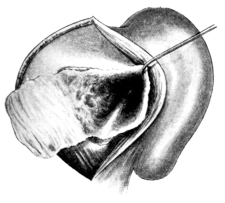

| 71. | Vaginal Hysterectomy | 171 |